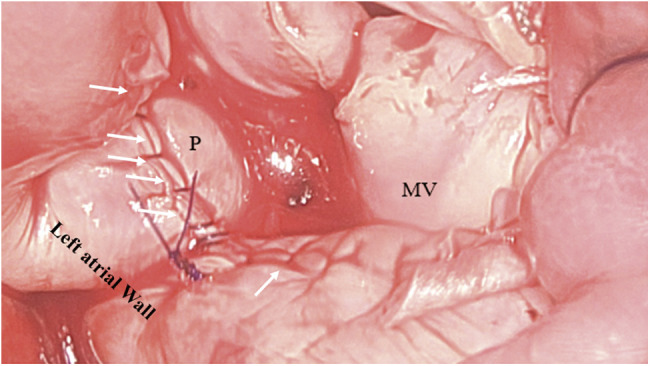

二尖瓣环钙化增加了二尖瓣置换术(MVR)的复杂性。标准程序要求在放置假体之前进行脱钙,然后重建二尖瓣环。虽然这是一种理想的技术,但由于相关的风险,并不是对每个病人都可行。单纯尝试瓣膜置换术而不进行适当的环脱钙会导致假体周围泄漏的高发生率,这使术后过程复杂化,并增加了发病率和死亡率。随着经导管治疗的进步,术后假体周围的反流可以用器械控制,经导管瓣膜植入术可以替代标准的瓣膜置换术;然而,这些替代策略并非没有其自身的局限性和缺点。在目前的报告中,我们提出了一种新的策略,用于一组有严重但非环性钙化的患者,以预防/减少MVR期间假体周围的反流。这包括在位于后方的钙棒上放置一个贴片,从而最大限度地减少后缝合线的张力,并控制任何假体周围的反流。这种修改已在总共9例病例中进行,早期结果可接受。

Mitral annular calcifications have been known to increase complexity during mitral valve replacement (MVR). Standard procedure requires decalcification followed by reconstruction of the mitral annulus prior to placing the prosthesis. While this is the ideal technique, it is not feasible in every patient due to the associated risks. The mere attempt at valve replacement without proper annular decalcification has been associated with a high incidence of periprosthetic leak which complicates the postoperative course and has been associated with increased morbidity and mortality. With the advances in transcatheter therapy, postoperative periprosthetic regurgitation can be managed with devices and primary transcatheter valve implantation could be alternative to standard valve replacement; however, these alternate strategies are not without its own limitations and drawbacks. In the current report, we present a novel strategy to be used in a select group of patients with severe but non-circumferential annular calcifications to prevent/minimize periprosthetic regurgitation during MVR. This involves placing a patch over the posteriorly located calcium bar, thus minimizing tension on the posterior suture line and contain any periprosthetic regurgitation if to develop. This modification has been performed in a total of nine cases with acceptable early results.